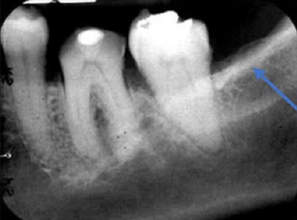

43. What is the anatomical structure indicated by arrow in this radiograph?

Maxillary Sinus The borders of the maxillary sinus appear on periapical radiographs as a thin, delicate, tenuous radiopaque line. In adults the sinuses usually extend from the distal aspect of the canine to the posterior wall of the maxilla above the tuberosity. In older adults the sinus may extend farther into the alveolar process, and in the posterior region of the maxilla its floor may appear considerably below the level of the floor of the nasal cavity. Anteriorly each sinus is restricted by the canine fossa and is usually seen to sweep superiorly, crossing the level of the floor of the nasal cavity in the premolar or canine region. Consequently, on periapical radiographs of